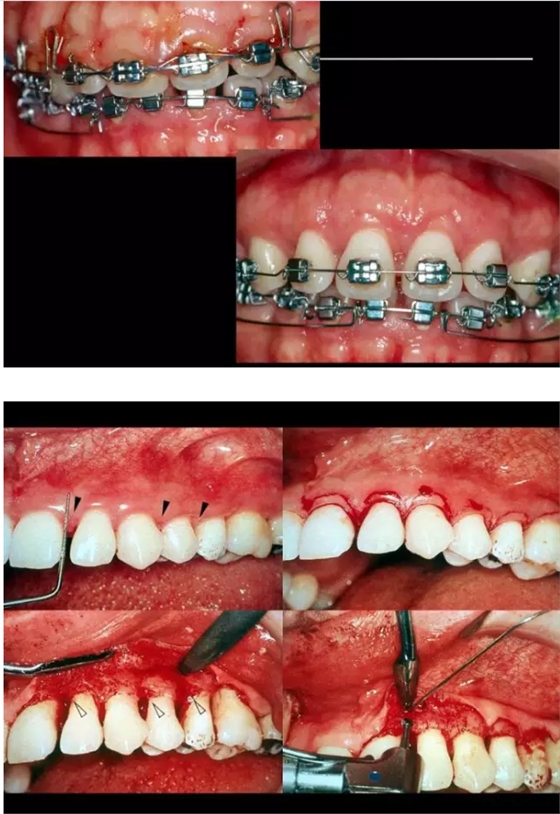

54.png

55.png

56.png

60.png